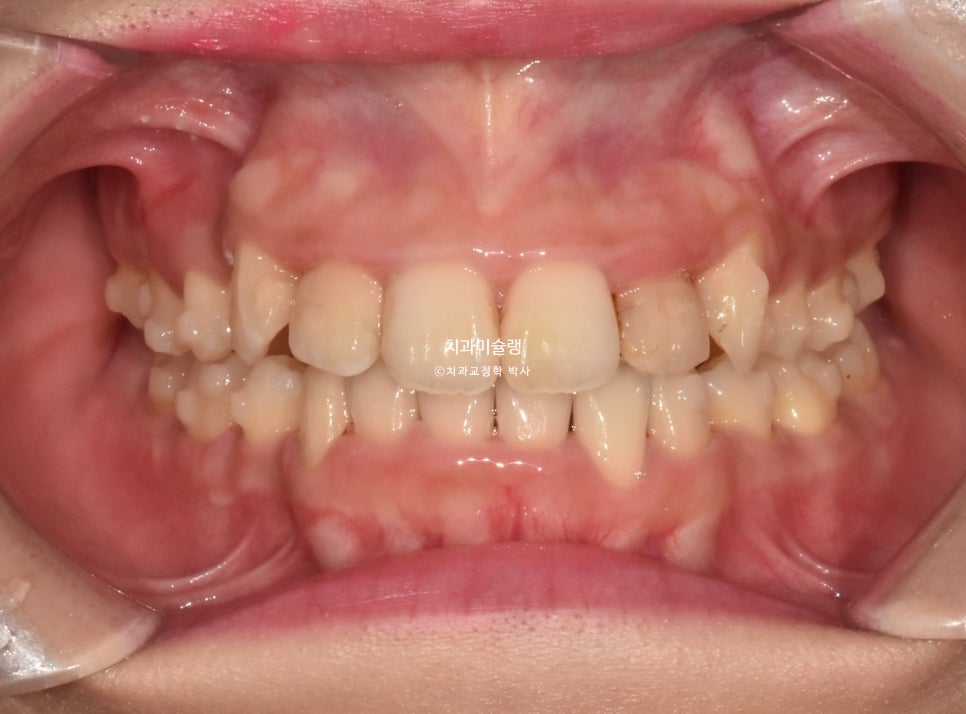

2023년 여름, 인비절라인 교정을 원해서 온 환자분 입니다.

닷니와 반대교합이 보입니다.

앞니에 갈색 부분은 예전에 레진으로 충치치료한 부분이 변색된 것입니다.

작은어금니 쪽에는 반대교합도 보입니다.

악궁이 소구치 부위가 안으로 쓰러져 찌그러진 모양입니다.

앞니뿐 아니라 어금니에도 여기저기 충치가 보입니다.

총생 (치아 삐뚤한 정도) 가 심하고 돌출감도 있어 작은어금니 4개 발치가 불가피한 상황입니다.